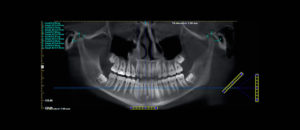

228 – Impacto de la CBCT en la toma de decisión del tratamiento relacionado a extracción de terceros molares impactados.

El objetivo del presente estudio fue evaluar los factores (referidos a la CBCT) que influyen en la toma de decisión en tratamientos para extracción de